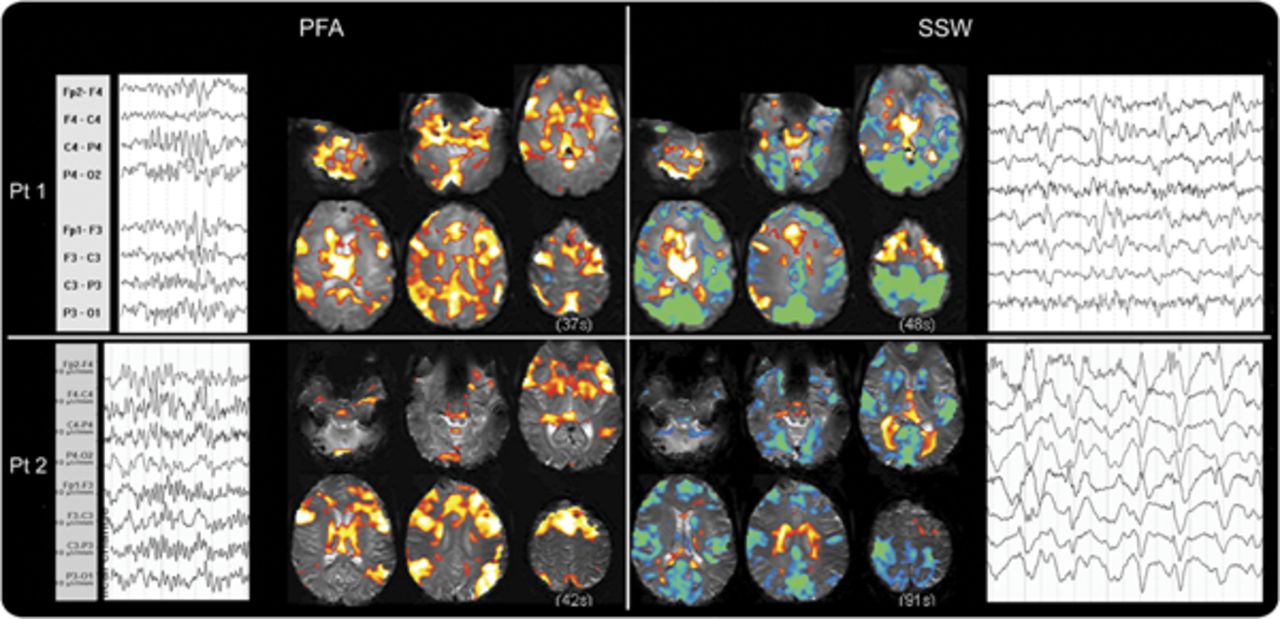

结果:同时用fMRI, PFA在6例,在西南偏南约9(2,都记录)。PFA事件显示几乎均匀增加血氧等级相关(粗体)信号“协会”皮质,以及脑干、基底节和丘脑。大胆的信号变化量显示为不同的模式与下降的许多领域大胆的信号,主要是在主要的皮质。前两患者callosotomy有单侧性的以及广义PFA。边音的PFA与一个半球PFA模式的版本我们报告在这里。

在所有患者6 PFA,皮质大胆的改变几乎完全是积极的信号。外显率的分布地图显示激活(图2一个;个案如图e 1上首页®网站www.首页neurology.org)。PFA-related大胆的增加主要影响广泛的额叶皮质“协会”地区,顶叶枕叶和颞叶,但似乎并没有意识到涉及初级皮层。

结合阈值SPM PFA的“外显率地图”(A)和(B)西南偏南约显示大脑皮层和皮层下的整体模式的激活和解除激活这些癫痫样的事件。颜色代表对象的数量规模与显著激活体素(黄色高于阈值的像素点为所有6科目PFA和9 f)。增加在大胆的信号显示在暖色和冷色的减少。没有大胆的反应主要在PFA皮质;初级运动、视觉和听觉皮层(箭头)没有激活或不激活体素,而所有这些领域显示减少大胆在f(同样的箭头在B)。在联合皮质(例如,箭头在顶叶皮层)强烈激活在量和没有大胆的在量的变化。这是真的协会地区除了一些地区的额叶皮质显示量的失活。皮层下结构,如脑干和尾状,显示激活量在PFA和失活。尽管个人更多的变化结果与量覆盖所有情况下导致这种识别的模式。大胆=血氧等级相关;PFA =阵发性快速活动; SPM = Statistical Parametric Mapping; SSW = slow spike and wave.

在5 6 PFA的数据集,有大胆的信号增加丘脑。大胆的信号增加尾状核和基底神经节也观察到在5 6例。单边模式时或者有单侧性的强调,PFA和大胆的信号变化的偏侧性与解剖病变,和最大的一侧丘脑参与与最大的一侧皮质的变化。

脑干显示增加大胆信号subcollicular水平与PFA的4 6例。小脑激活被认为在大多数主题(5 6)。

良好的样本PFA和量都记录在2主题,和这两个人演示模式的基本特征在整个集团(图3)。

缓慢的上升和波。

量排放记录9例。他们与正面和负面的皮质大胆的混合信号的变化(图2、e 1和飞行)。

不像PFA,皮质是西南偏南约模式变量(图飞行)。的一部分,这可能是由于有限的数据量(患者9、10、13)。患者6,7,8弱难以解释的激活。患者1、2和5有强烈激活外显率最佳解释的引用映射(图2)。这表明失活往往是在初级皮质(电动机、视觉和听觉)和中线顶叶皮层。有分散在其他领域积极激活皮层,特别是额叶皮层的某些地区。

大胆的信号变化4例患者出现丘脑在场。这些都是双边积极2(病人1和5),双边-在一个病人(6),和积极的一面和消极变化在另一个病人(2)。

有4例患者出现大胆的尾状核的活动减少,这是外显率的地图(图2)。脑干显示大胆的信号变化subcollicular水平4例(2增加和减少2)。

我们的研究的主要发现是PFA和f (LGS)的2定义电记录的特性有独特和明显不同的大脑皮层和皮层下大胆的信号变化模式。PFA显示了一个独特的、分散和一致的“激活”,大脑的许多地方,特别是在协会皮层(图2)。

PFA显示激活在广泛领域的皮层,但似乎备用主皮质。PFA显示增加大胆信号的皮层下结构包括丘脑、基底神经节,和脑干,所有已知的“联合皮层有广泛的联系。“这观察激活在许多领域与协会有关皮层和皮层下系统,但不包括初级皮层,导致我们称之为网络激活,我们看到在PFA”扩散协会网络激活”(DANA)。此外,在大多数情况下,不同的左/右或前/后头皮排放的重点体现在前/后招聘比例左/右或分散的网络。